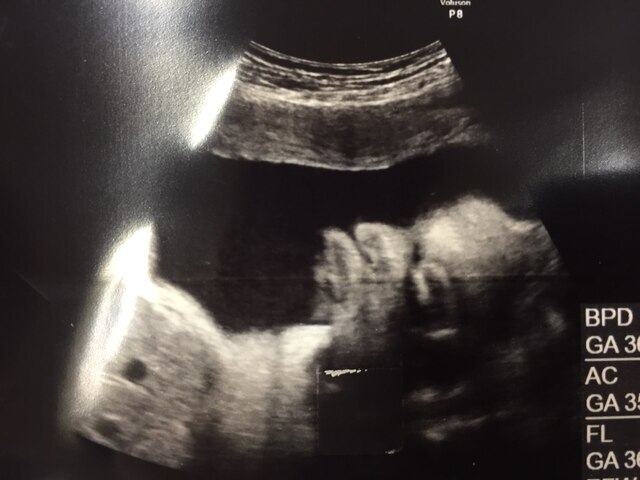

37週2日(37w2d・男の子)|homiho さん(27歳)

エコー写真撮影時のエピソード:

臨月に入ってお腹が重くて何をするのも大変でした。でもお腹の中で元気に暴れまわってるのを感じると、痛みよりももうすぐ会えるんだなーとか胎動を感じられるのもあと少しなんだなーとわくわくして毎日を過ごしていました。この時のエコー写真で初めて正面の顔を見ることができて、パパとあまりにもそっくりだったので両家の家族や共通の友達と大笑いしたのを覚えています。この時点で推定体重が3200gになっていて、初めての出産でこんなに大きい子を無事に普通分娩で産めるのか不安でしたし、体を動かすのは大変な時期でしたが家族に支えられて楽しく毎日を過ごしていました。